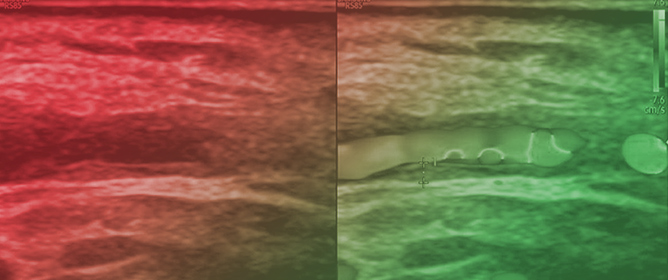

The Middle Meningeal Artery (MMA) occupies a pivotal role in the pathophysiology of migraine, functioning as a vascular and neuroimmune interface that precipitates the characteristic pulsatile pain. The inhibition of this pathophysiological cascade has been investigated as a therapeutic strategy. However, fewer than a dozen centers globally have disseminated procedural or mechanistic data. Given the nascency of this field and the imperative for standardization, the present review synthesizes mechanistic and clinical evidence underpinning intra-arterial pharmacological modulation of the MMA for migraine management. Methods: A focused narrative review was undertaken, drawing upon select but influential studies from pioneering research groups investigating intra-arterial interventions targeting the MMA. The extant literature was thematically categorized and organized according to the loci of cascade interruption and their corresponding clinical outcomes. Results: Since 2009, intra-arterial therapies for severe headache syndromes have evolved, initially utilizing nimodipine for vasospasm-related headaches, progressing to verapamil for reversible cerebral vasoconstriction, and more recently, lidocaine for refractory or status migrainosus, occasionally in conjunction with MMA embolization. Contemporary research uses language that conceptualizes migraine as an immunologically mediated neurovascular disorder, as opposed to a purely vascular or neuronal entity. Recent investigations have identified interleukins such as Interleukin-1β, Tumor Necrosis Factor-α, and Interleukin-6 as critical amplifiers of trigeminovascular activation. Purinergic signaling through the P2X3 receptor and the P2Y13 receptor, in conjunction with pituitary adenylate cyclase-activating polypeptide and vasoactive intestinal peptide pathways, has been implicated in the modulation of MMA excitability and neuropeptide release. The development of novel calcitonin gene-related peptide receptor antagonists, such as zavegepant, further substantiates the artery’s significance as a pharmacological target. Conclusions: These findings support a shift toward immune-modulating intra-arterial therapeutic strategies, with migraine interventions targeting cytokine and neuroimmune signaling within the MMA, rather than relying exclusively on vasodilatory mechanisms.